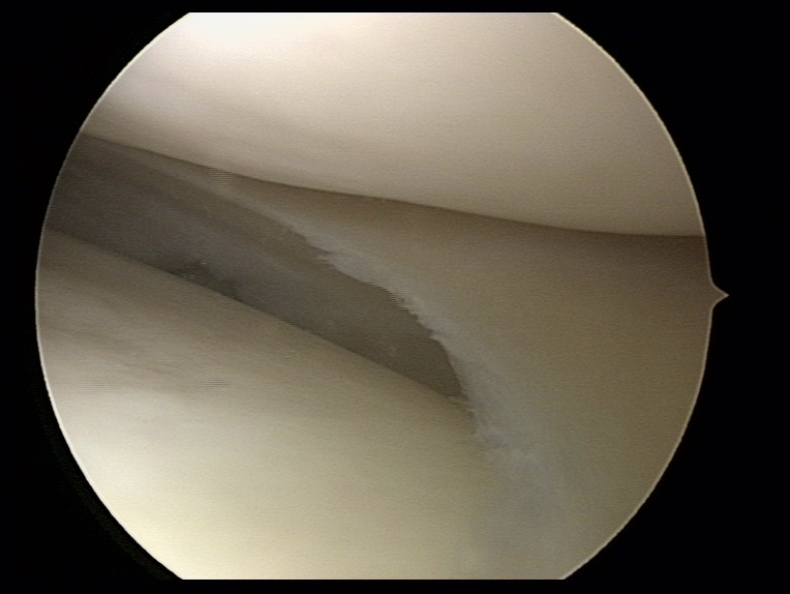

In afbeelding 2 ziet u een gezonde meniscus en in afbeelding 3 een degeneratieve meniscus die in beeld zijn gebracht bij een artroscopie (kijkoperatie) van de knie.